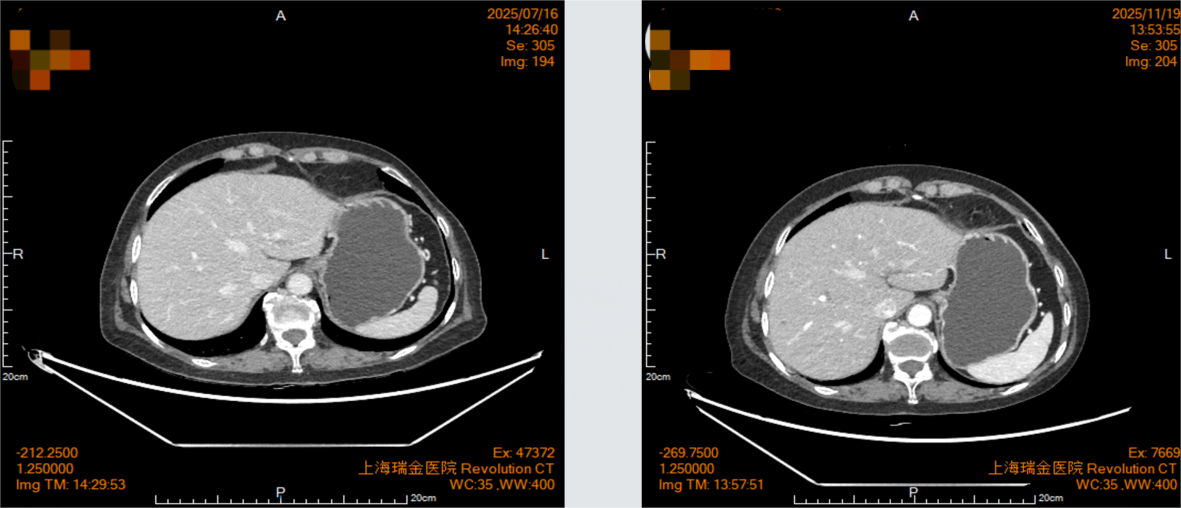

2025年7月16日复查影像学显示,贲门癌化疗后,贲门胃壁稍增厚;双肺间质性改变。

2025年11月19日复查影像学显示,贲门癌化疗后,贲门胃壁稍增厚;贲门部肿物及转移淋巴结较前明显退缩,影像表现为接近CR(无可评价病灶)。